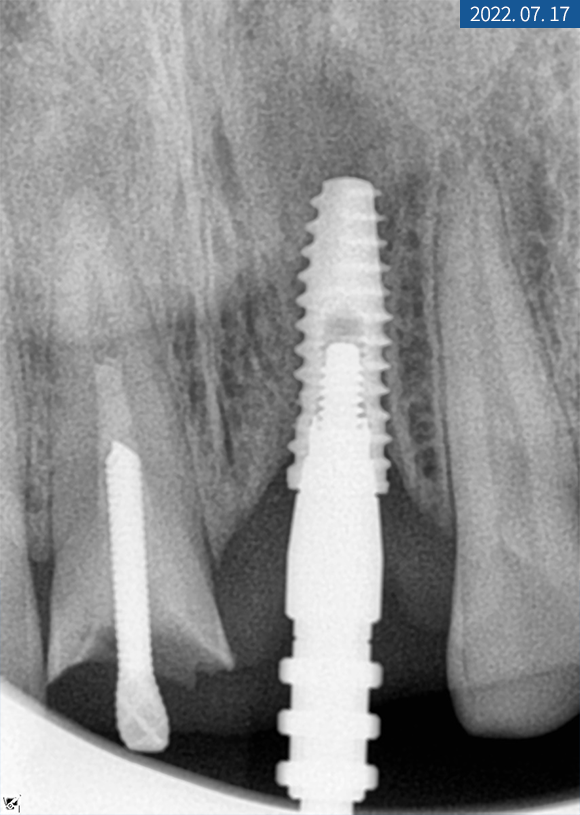

앞니는 차폐막을 걷고

커버 스크류를 뺀 후

힐링 지대주를 연결해 드렸는데요.

한 달 후 잇몸이 잘 아문 것을 확인하고

대구치와 동일하게

상부 보철물 제작에 들어갔습니다.

#11번은 인공 나사를 심고 힐링 어버트먼트를

바로 연결해서 잇몸을 만들었습니다.

3개월 후 골 유착을 확인하고

교합과 인상 채득을 한 다음 크라운 제작을 위해

색상 대조 후 기공소에 의뢰했습니다.

한 달 후 치근단 사진을 찍어보니

주위 염증 없이 이식된 자리에

잘 위치하고 있었습니다.